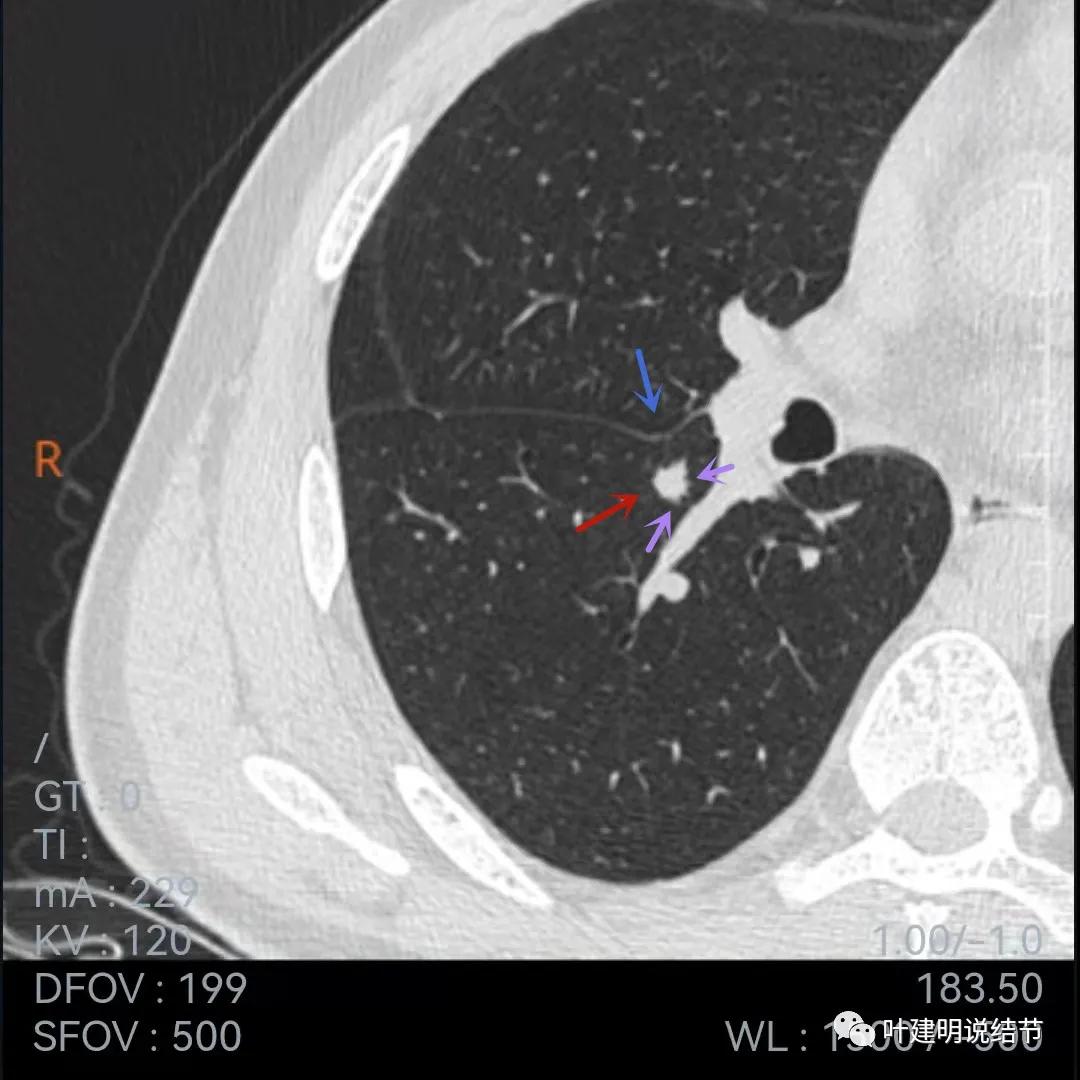

再来看当地医院的靶扫描:

病灶叶间胸膜凹陷,有细毛刺(紫色箭头),但毛刺与病灶大小相比感觉长了点

中间密度还是略低(黄色箭头),胸膜牵拉仍明显(蓝色箭头)

细毛刺(紫色)、胸膜凹陷(蓝色)以及中间偏低密度(黄色)

上图棘突样征象较明显(紫色箭头)

此图不太舒服,胸膜牵拉、表现不平、有微血管征(桔色),但边缘似有少许晕征(绿色),若真是晕征,也是符合肉芽肿性的

上图也示胸膜牵拉、棘突样征,桔色所指似血管进入,但又不太像,增粗的淋巴结管?血管边的是淋巴结吗?不清楚,先不管它